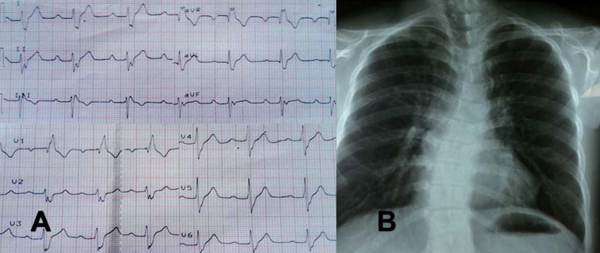

En el electrocardiograma destaca PR prolongado, bloqueo completo de rama derecha y hemibloqueo anterior izquierdo. En la radiografía de tórax se evidencia hiperflujo pulmonar y escoliosis de la columna dorsal con concavidad izquierda (figura 2). El ecocardiograma transtorácico reportó comunicación interauricular tipo ostium primum de 22 mm, comunicación interventricular de 15 mm totalmente ocluida por velo septal tricuspídeo convirtiendo un canal AV intermedio en un canal AV parcial e hipertensión pulmonar leve.

A. Electrocardiograma, aVR, aVL y aVF registradas a 1mV/5mm: Ritmo sinusal, 75 lpm, Eje QRS - 90°, intervalo PR de 240 ms, complejo QRS de 120 ms con morfología de bloqueo completo de rama derecha y hemibloqueo anterior izquierdo. B. Radiografía A-P: Situs solitus, índice cardiotorácico de 0,48, cono de arteria pulmonar prominente, aumento de la trama vascular, escoliosis de la columna dorsal.